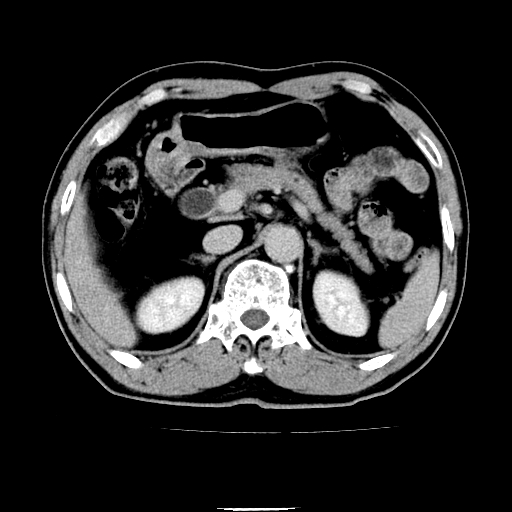

以下是引用chenqiong在2010-3-25 20:56:00的发言:[br]1、胆囊炎,胆囊息肉[br]2、肝内胆管及胆总管扩张,胆总管下端结石[br]3、十二指肠乳头旁憩室

以下是引用zxl51642在2010-3-26 10:47:00的发言:[br]胆囊炎,胆囊息肉,胆总管扩张,但未看到明显肿块,肝内胆管扩张不像恶性,炎性狭窄或阴性结石可能吧,建议mrcp,右肾小囊肿